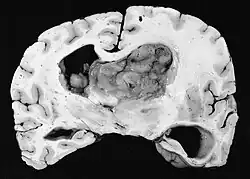

Subependymal giant cell astrocytoma (SEGA, SGCA, or SGCT) is a low-grade astrocytic brain tumor (astrocytoma) that arises within the ventricles of the brain.[1] It is most commonly associated with tuberous sclerosis complex (TSC). Although it is a low-grade tumor, its location can potentially obstruct the ventricles and lead to hydrocephalus.

A NIH Consensus Conference report in 1999 recommends that any SEGA that is growing or causing symptoms should be surgically removed.[2] Tumors are also removed in cases where a patient is suffering from a high seizure burden.[1] If a tumor is rapidly growing or causing symptoms of hydrocephalus, deferring surgery may lead to vision loss, need for ventricular shunt, and ultimately death. Total removal of the tumor is curative.

After complete surgical removal, a SEGA tumor does not grow back. They do not metastasize to other parts of the body. However, the patient is still at risk for, and often develops, new tumors arising from subependymal nodules elsewhere in the ventricular system.